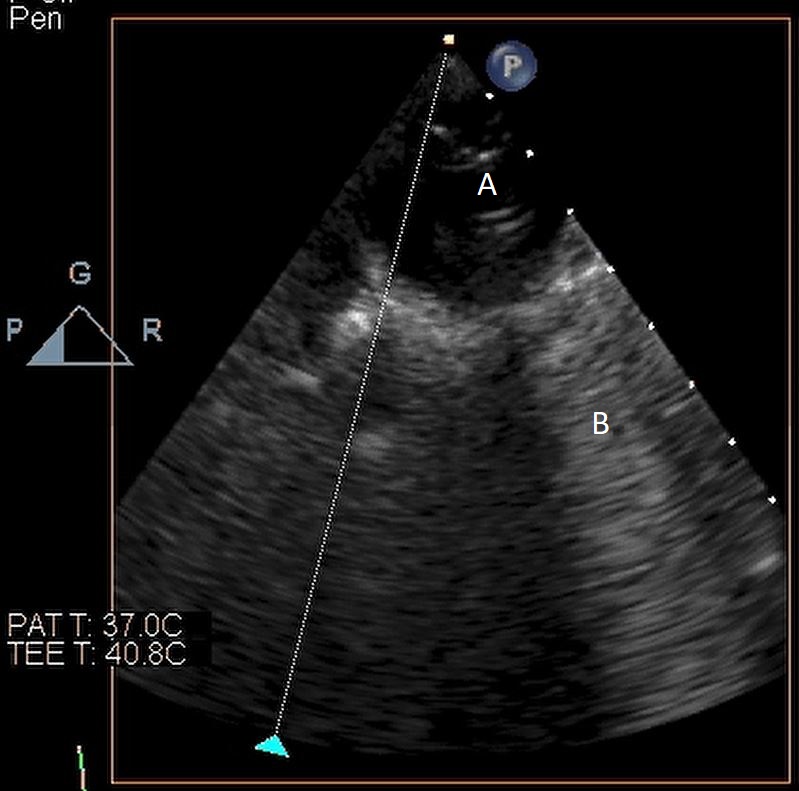

The intra-aortic balloon pump is a percutaneously placed counter pulsation device which helps in decreasing afterload as well as augmenting coronary perfusion. Initially developed in the 1960s it is the oldest MCS device and given its simplicity, cost effectiveness, and ease to implant and explant, it is the most commonly used temporary support device [6]. Although it is typically placed in the cardiac catheterization lab under fluoroscopic guidance, TEE can be utilized to help in its placement in the intubated patient in the intra-operative setting. The femoral artery is the most common site of placement however they can on occasion be placed in alternative sites such as the axillary artery or directly into the aorta [7, 8]. When placed via the femoral artery, it is threaded over a guidewire. TEE can be used to visualize both the guidewire as well as the tip of the IABP catheter during placement (Fig. 1) [9]. Ideal positioning of the balloon tip is 1–2 cm distal to the left subclavian artery to derive maximal hemodynamic benefit [10]. Positioning can be confirmed by visualizing the descending aorta and then withdrawing the TEE probe until the left subclavian artery and aortic arch are visualized. Upon activation of the balloon pump the gas filled balloon will cause shadowing and reverberation artifacts (Fig. 2). Its presence can be used as confirmation of proper function of the device. If these artifacts are not seen or bubbles are visualized in the aorta, rupture of the IABP should be suspected [9]. In addition to hemodynamic monitoring with a Swan-Ganz catheter, TTE can be used to monitor LV function after IABP placement and can help guide weaning of IABP support. It can also visualize any new or worsening aortic regurgitation. Given that IABPs work by reducing afterload, on rare occasions they can precipitate dynamic outflow tract obstruction and paradoxically worsen cardiogenic shock. Examples include patients with a relatively preserved basal or septal myocardial function in scenarios such as takotsubo cardiomyopathy or acute myocardial infarctions. Doppler imaging and color flow doppler can be used to identify such scenarios [11].

Fig. 1.TEE demonstrating IABP in descending aorta (A).

TEE demonstrating IABP in descending aorta (A) with reverberation artifact seen behind it upon activation (B).